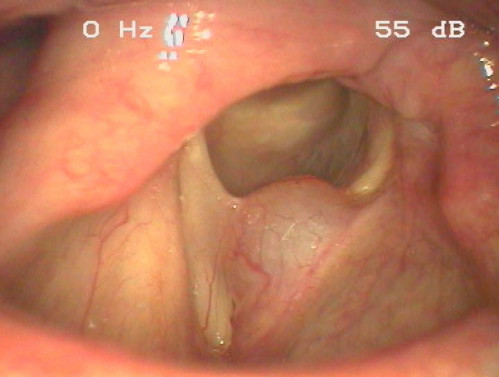

ICD: Q31.3

Eine 63-jährige Patientin klagt über Missempfindungen (Fremdkörpergefühl) auf Höhe des Kehlkopfes. Bei längerem Sprechen empfindet sie Stimmanstrengungen. Atmung und Schlucken sind nicht beeinträchtigt. Sie hat auch keinerlei sonstige Beschwerden oder Erkrankungen.